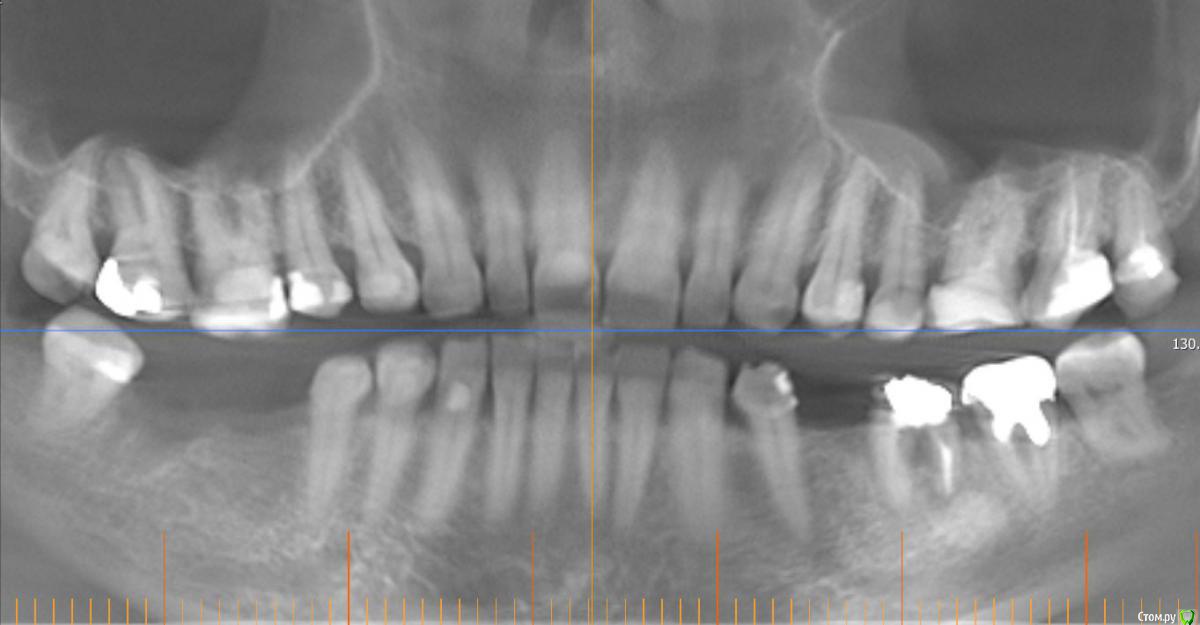

Monkey Опубликовано 6 сентября, 2015 Автор Поделиться Опубликовано 6 сентября, 2015 Про ВЧ речь идет?Были брекеты вверху? не думаю, что это поможет. при отсутвие должного оверджета не получится протрузии, а значит и разворачиваться некуда будет. и прямоугольная дуга не поможет при таком дефиците места. процесс пойдет только тогда, когда появится место. это либо 1. создание оверджета (за счет ВЧ), или 2. сепарация НЧ 3. как вариант дистализация премоляров (если окклюзионные контакты позволяют (как сейчас по прикусу в боковых отделах? есть фото?) ) Нет, брекетов на вч не было. Фотографии боковых отделов есть только июньские. Дистализировать там больше нельзя.Выходит вариант один - сепарировать весь фронт? Ссылка на комментарий

Yana guapa Опубликовано 7 сентября, 2015 Поделиться Опубликовано 7 сентября, 2015 Дистализировать там больше нельзя.Выходит вариант один - сепарировать весь фронт? или ставить брекеты наверх)) справа 2 класс, ротирована НЧ вправо походу. (средние линии не совпадают, а при открытии рта выравниваются). у вас все равно компромиссное лечение (не до идеала, судя по бугорковому смыканию, наличию 8-к, заваленным 7-кам,....), то тогда и посепарировать можно. по-другому не впихнуть резцы. 1 Ссылка на комментарий

Monkey Опубликовано 7 сентября, 2015 Автор Поделиться Опубликовано 7 сентября, 2015 или ставить брекеты наверх)) справа 2 класс, ротирована НЧ вправо походу. (средние линии не совпадают, а при открытии рта выравниваются). у вас все равно компромиссное лечение (не до идеала, судя по бугорковому смыканию, наличию 8-к, заваленным 7-кам,....), то тогда и посепарировать можно. по-другому не впихнуть резцы. думаю там преждевременный контакт на 8-ке левой, вот она и скатывается. Яна, спасибо большое за советы! Ссылка на комментарий

Kazankov.Egor Опубликовано 21 сентября, 2015 Поделиться Опубликовано 21 сентября, 2015 или ставить брекеты наверх)) справа 2 класс, ротирована НЧ вправо походу. (средние линии не совпадают, а при открытии рта выравниваются). Если бы вы понимали насколько это смелое заявление) дельного совета без полной диагностики тут не дать) даже в отношении единственного зуба. у вас все равно компромиссное лечение (не до идеала, судя по бугорковому смыканию, наличию 8-к, заваленным 7-кам,....), то тогда и посепарировать можно. по-другому не впихнуть резцы. Ссылка на комментарий